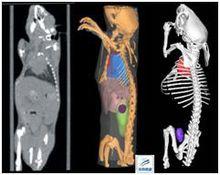

小鼠活體成像動物材料

骨、牙齒、肺、腎、肝、腦等組織的血管生長情況。

Micro-CT腫瘤研究